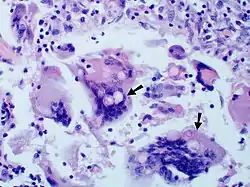

Granuloma with early suppuration. Fungal organisms difficult to recognize at this low magnification.

Large yeast-like fungi seen within giant cells at arrows.

Large yeast-like fungi seen within giant cells at arrows.Budding yeasts in cytoplasm of giant cells at arrows. Broad-based budding and double contoured cell wall seen in the giant cell in the center is characteristic of Blastomyces dermatitidis.